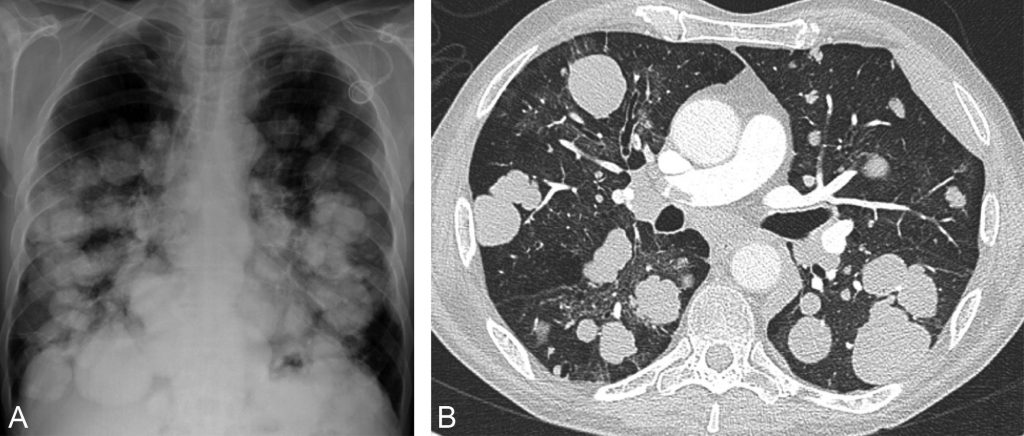

Fig. 101.5. Radiographie thoracique de face (A) et scanner thoracique (B).

Multiples macronodules réalisant une image en « lâcher de ballons ». Il s’agissait de métastases d’un carcinome bronchique non à petites cellules indifférencié. À noter sur la coupe scanographique l’existence d’une embolie dans l’artère pulmonaire droite.

Source : CERF, CNEBMN, 2022.